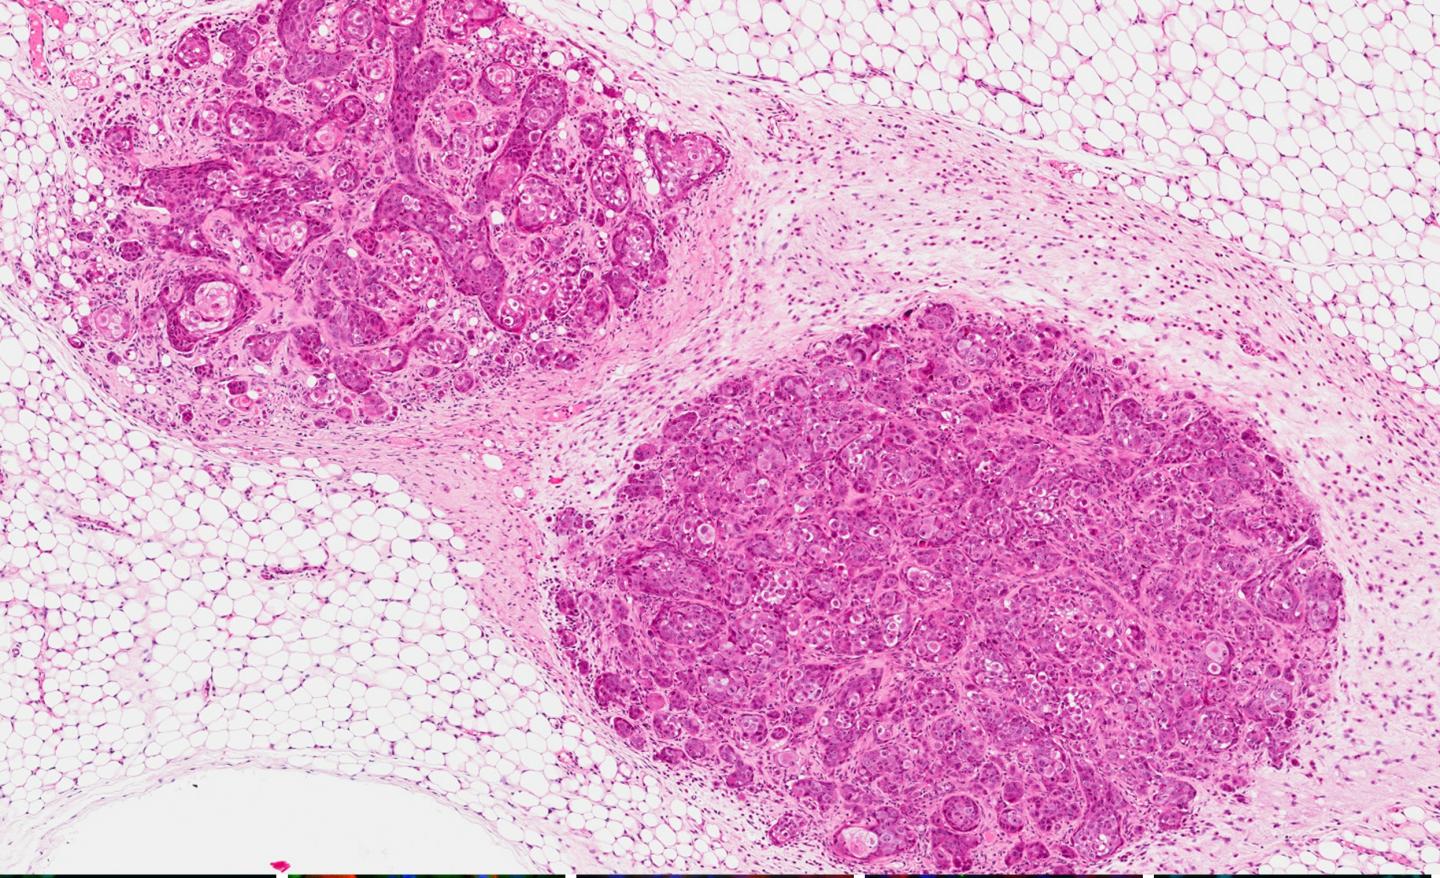

The first clinically-relevant mouse model of human breast cancer to successfully express functional estrogen receptor positive (ER+) adenocarcinomas has been developed by researchers at Lawrence Berkeley National Laboratory (Berkeley Lab). The tumors generated in this system bear a striking resemblance to the class of tumors found in the vast majority of women with breast cancer, and especially to those whose cancer proves treatment-resistant. This model should be a powerful tool for testing therapies for aggressive ER+ breast cancers and for studying the biology and etiology of luminal cancers -- the most prevalent and deadliest forms of breast cancer.

In a study led by renowned breast cancer authority Mina Bissell, xenografts of the cell line '184AA3' consistently formed human estrogen receptor positive (ER+) luminal breast tumors in mice. ER+ luminal tumors account for nearly 80-percent of all newly diagnosed breast cancers each year and more women die from treatment-resistant luminal breast cancer than of all other breast cancer types combined.

ER+ luminal breast cancers are adenocarcinomas, meaning they start in cells with a secretory function, in this case the milk-producing luminal cells of the breast. Despite the prevalence of ER+ luminal tumors and their frequent (nearly 30-percent) conversion to treatment resistance, there are very few models of this cancer subtype available for the development of drugs. Further, the models that do exist have questionable clinical relevance in that they generate tumors that look and behave quite differently than human tumors.

"To determine the tumorigenicity of 184-derived cell lines, we orthotopically xenografted each cell line possessing anchorage-independent growth into the fat pads, then monitored them for tumor growth in the mammary gland," says Hines, a scientist and a member of Bissell's research team. "Whereas most xenografts resulted in either squamous carcinomas or no tumors at all, 184AA3 consistently produced adenocarcinomas closely resembling clinical breast tumors."